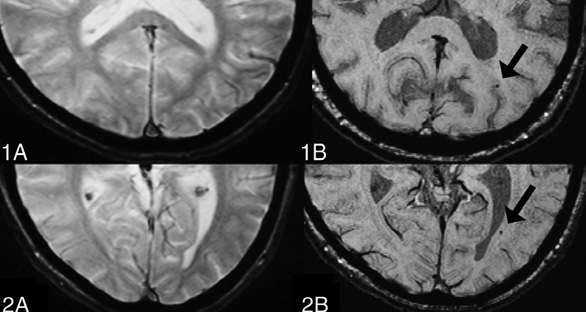

TMBs are detected in 27% of mild, 47% of moderate, and 58% of severe TBI cases. In contrast to microbleeds associated with small vessel disease or other non-traumatic conditions, traumatic CMBs exhibit distinct characteristics in terms of their location and appearance [17]. These trauma-induced lesions are frequently found in the corpus callosum and at the interface between the grey and white matter. Moreover, traumatic CMBs typically display a more radial and linear pattern, often aligning with the perivascular spaces. This configuration differs noticeably from the rounded shape commonly observed in CMBs linked to small vessel disease (SVD) [17]. These differences in distribution and morphology can aid in distinguishing traumatic from non-traumatic microbleeds in neuroimaging. However, absolute differentiation between these lesions remains challenging.

SWI has several limitations, including its reliance on phase images that may fail to accurately depict local anatomical structures and its sensitivity to the orientation of objects relative to the magnetic field. Interpreting complex regions, such as the basal ganglia, is particularly challenging with SWI due to these constraints. To address these limitations, Quantitative Susceptibility Mapping (QSM) has been proposed as a superior alternative, offering notable advantages, especially in detecting microbleeds in mild traumatic brain injury (mTBI) [21]. Unlike SWI, QSM provides a more precise and quantitative assessment by directly measuring tissue susceptibilities, which improves the accuracy in evaluating the size and concentration of microbleeds. Additionally, QSM minimizes the common SWI artifacts, such as blooming effects, resulting in clearer and more reliable imaging, particularly in complex anatomical regions where SWI may struggle. QSM also enhances contrast sensitivity, allowing for the detection of smaller or more subtle microbleeds that might be missed with SWI. Furthermore, QSM has the ability to differentiate between microbleeds and other brain deposits, like calcifications, ensuring a more accurate diagnosis and effective monitoring of brain injuries [21]. Overall, QSM offers a more advanced and effective approach for the assessment and characterization of microbleeds, supporting improved clinical outcomes and more precise treatment planning.